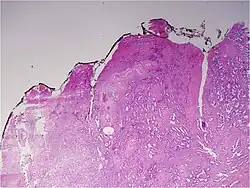

Histologic patterns

A pathologist microscopically examines the biopsy specimen for certain "Gleason" patterns. These Gleason patterns are associated with the following features:

- Pattern 1 – The cancerous prostate closely resembles normal prostate tissue. The glands are small, well-formed, and closely packed. This corresponds to a well differentiated carcinoma.

- Pattern 2 – The tissue still has well-formed glands, but they are larger and have more tissue between them, implying that the stroma has increased. This also corresponds to a moderately differentiated carcinoma.

- Pattern 3 – The tissue still has recognizable glands, but the cells are darker. At high magnification, some of these cells have left the glands and are beginning to invade the surrounding tissue or having an infiltrative pattern. This corresponds to a moderately differentiated carcinoma.

- Pattern 4 – The tissue has few recognizable glands. Many cells are invading the surrounding tissue in neoplastic clumps. This corresponds to a poorly differentiated carcinoma.

- Pattern 5 – The tissue does not have any or only a few recognizable glands. There are often just sheets of cells throughout the surrounding tissue. This corresponds to an anaplastic carcinoma.

In the present form of the Gleason system, prostate cancer of Gleason patterns 1 and 2 are rarely seen. Gleason pattern 3 is by far the most common.

The Gleason grade is based on tissue architectural patterns rather than purely cytological changes. These tissue patterns are classified into 5 grades, numbered 1 though 5. Lower numbers indicate more differentiation, with pattern 5 being the least differentiated.[4][7] Differentiation is the degree to which the tissue, in this case the tumor, resembles native tissue. Greater resemblance (lower grade) is typically associated with a better prognosis.